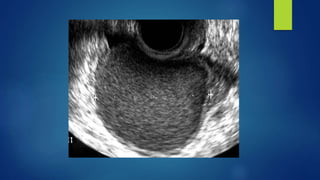

 TVS for follicular scanning

Diagnosis: TVS